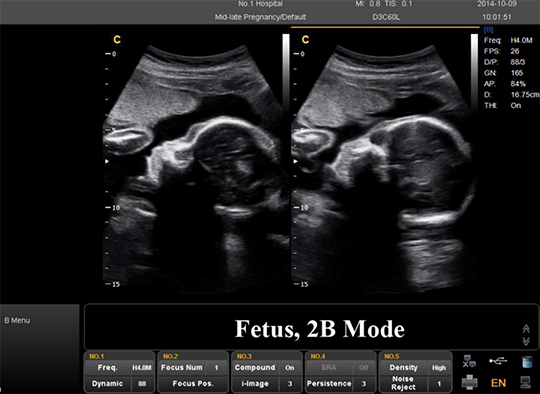

Echographie 2D

Toutes les ultrasons utilisent des ondes sonores pour créer une image. L'ancien standard est une image 2D ou bidimensionnelle. Il est utilisé comme méthode traditionnelle depuis des années. Ils fournissent des images noires et blanches plus plates et bidimensionnelles de votre bébé. L'échographie 2D vous donne des contours et des images d'apparence plate, mais elle peut être utilisée pour voir les organes internes du bébé. Ceci est utile pour diagnostiquer les anomalies cardiaques, les problèmes de reins et d’autres problèmes internes potentiels.

Échographie 2D